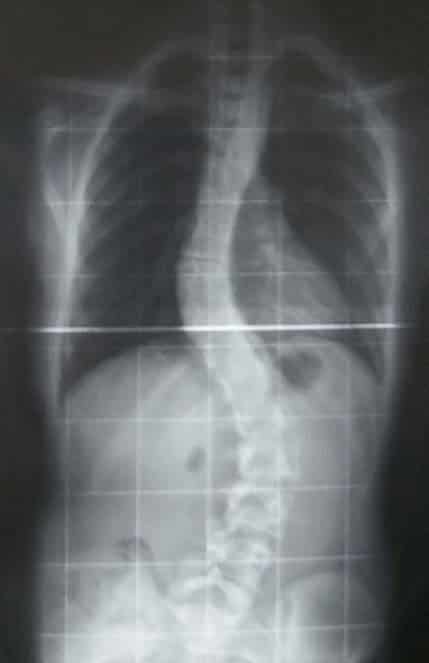

• Scoliosis – lateral curvature of the spine, usually of unknown cause.

Fig 1.5 - Radiograph of scoliosis of the spine.

Fig 9

Radiograph of scoliosis of the spine.